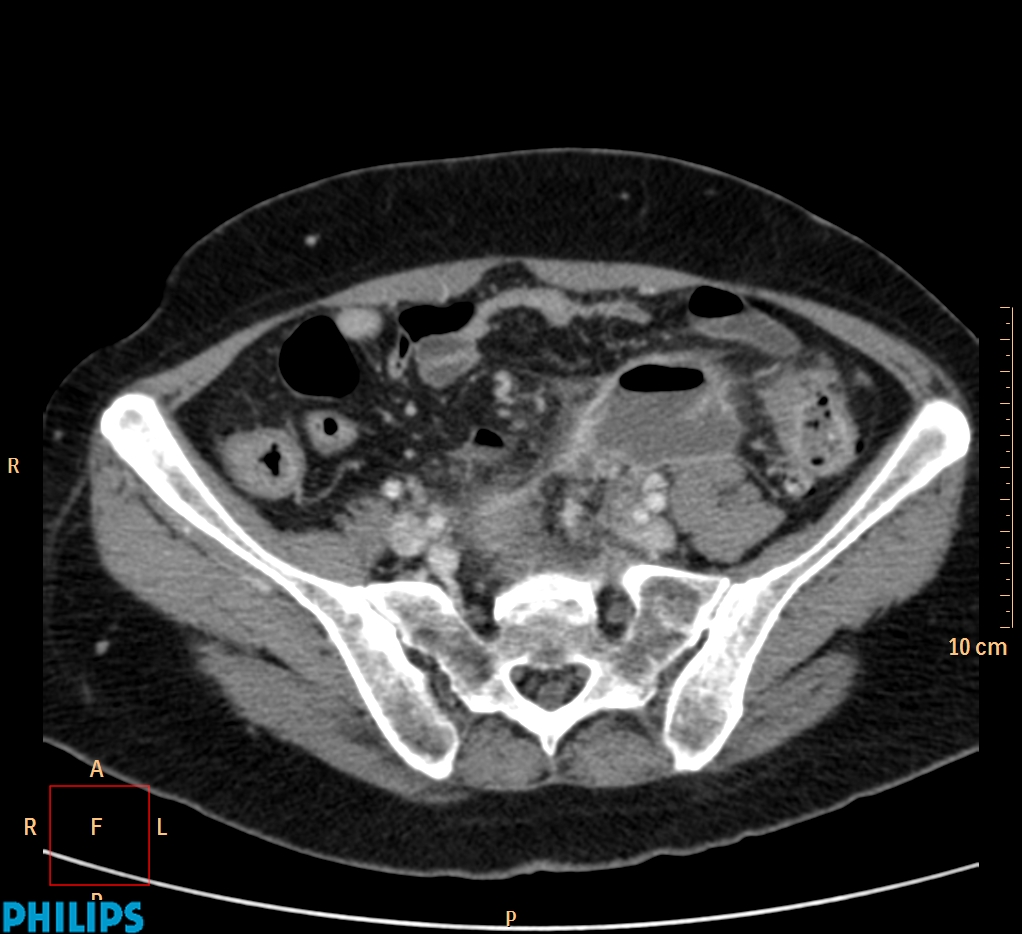

ΕΚΚΟΛΠΩΜΑΤΑ ΠΑΧΕΟΣ ΕΝΤΕΡΟΥ Posted by ΙΠΠΟΚΡΑΤΕΙΟ ΙΩΑΝΝΙΝΩΝ | Dec 16, 2020 | ΠΕΠΤΙΚΟ | 0 ΚΛΙΝΙΚΑ ΣΤΟΙΧΕΙΑ – ΙΣΤΟΡΙΚΟ υποτροπιάζοντες επαναλαμβανόμενοι πυρετοί κυρίως απογευματινές ώρες ΕΡΓΑΣΤΗΡΙΑΚΟΣ ΕΛΕΓΧΟΣ ΑΠΕΙΚΟΝΙΣΤΙΚΟΣ ΕΛΕΓΧΟΣ διακρίνονται τα αποστήματα στην ελάσσονα πύελο, καθώς και εκκολπώματα με εικόνα πάχυνσης του τοιχώματος του σιγμοειδούς ΣΥΖΗΤΗΣΗ